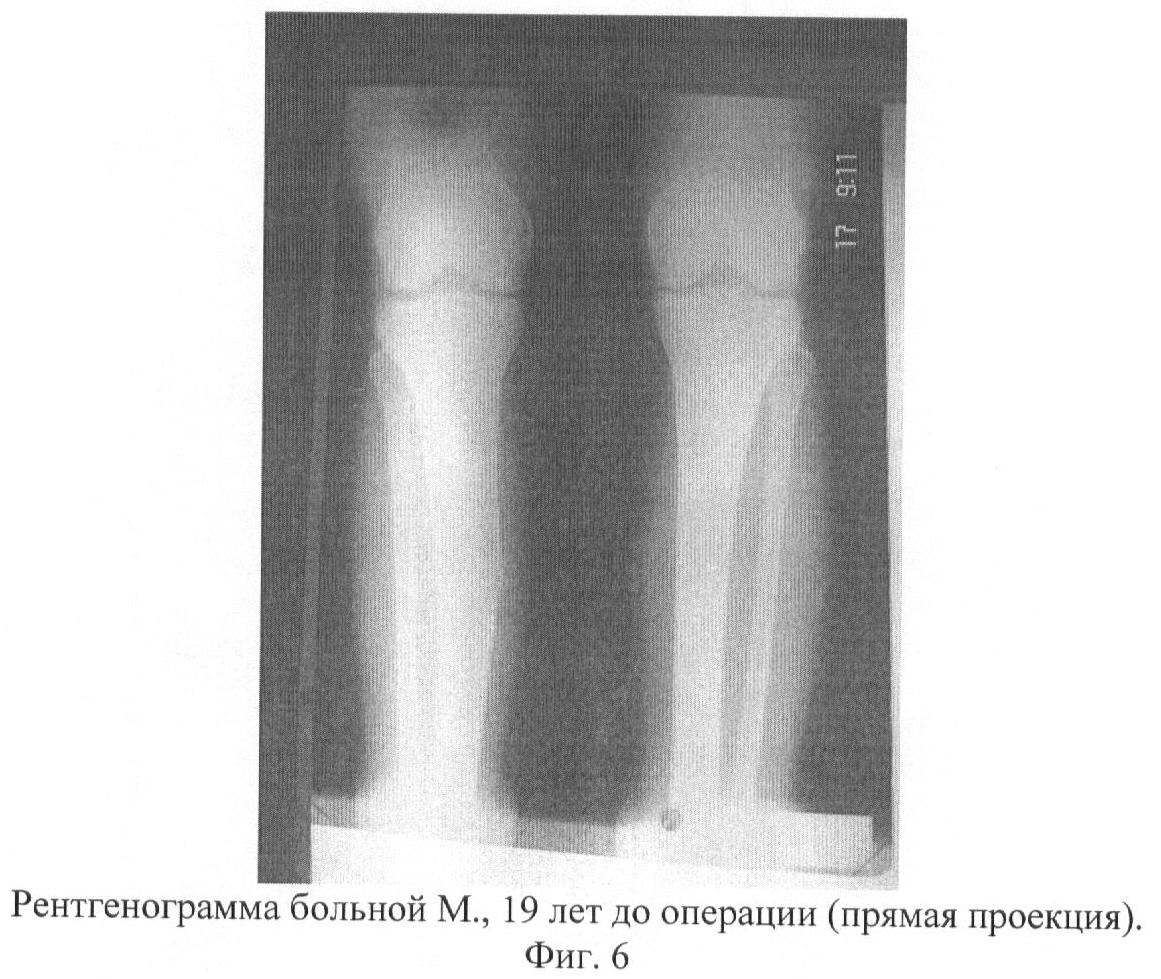

Больной проведено обследование: компьютерная томография обеих голеней, рентгенография, операционная биопсия костной ткани и полости кисты (цитологическое, гистологическое и бактериологическое исследование костной ткани). Данные гистологического, цитологического исследования: атипичные клетки не выявлены. Роста микрофлоры при бактериологическом посеве не обнаружено. Имеется опасность патологического перелома в зоне очага аневризмальной кисты, так как толщина кортикального слоя костной ткани составляет 1-2 мм. (фиг.5-7).